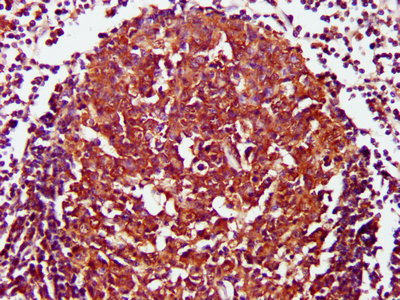

IHC image of CSB-PA08235A0Rb diluted at 1:800 and staining in paraffin-embedded human lymph node tissue performed on a Leica BondTM system. After dewaxing and hydration, antigen retrieval was mediated by high pressure in a citrate buffer (pH 6.0). Section was blocked with 10% normal goat serum 30min at RT. Then primary antibody (1% BSA) was incubated at 4°C overnight. The primary is detected by a biotinylated secondary antibody and visualized using an HRP conjugated SP system.